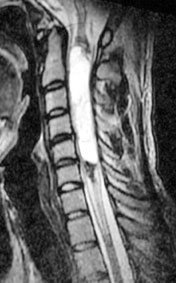

Die Abklärung mittels MRI (Bild 1und 2) ergibt den Befund eines volumineusen intramedullären Tumors, der sich von C3 nach C6 erstreckt. An den Tumorpolen zeigt sich eine zystische Komponente. Der solide Anteil des Tumors nimmt das Kontrastmittel auf. Angesichts der Grösse der Läsion sowie der progredienten neurologischen Ausfälle muss dem Patienten ein chirurgischer Eingriff empfohlen werden. Das Ziel des operativen Eingriffs ist es, einerseits die Diagnose zu erzwingen, andererseits die Läsion so komplett wie möglich zu entfernen, um eine drohende Tetraplegie zu verhindern.